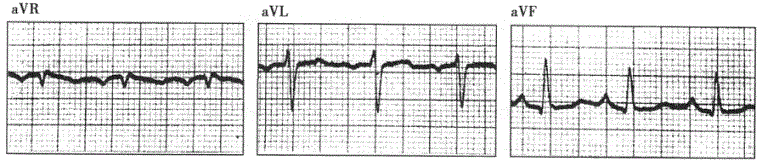

问题 患者女性,76岁,慢性咳喘33年,临床诊断慢性肺源性心脏病。心电图检查如下图所示。 ? ? ? 以下为诊断右心室肥大的依据,但应除外

选项 A.V导联出现q波 B.电轴显著右偏 C.V导联呈rsR′型; D.V导联R/S<1 E.有慢性肺源性心脏病史

答案 C